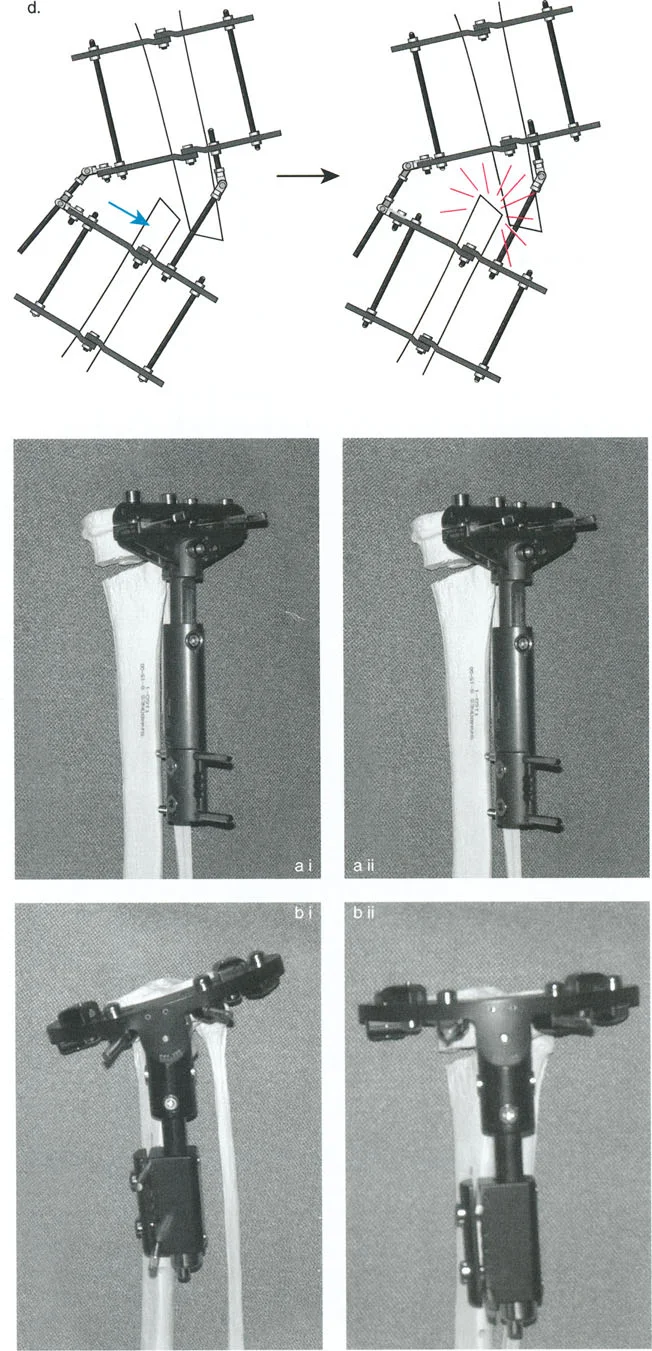

- مثبتات إليزاروف الدائرية الكلاسيكية: تتكون من حلقات معدنية متصلة بالعظم بأسلاك رفيعة، وتسمح بتصحيح متعدد المستويات.

- أنظمة الهيكسابود الحديثة (مثل جهاز تايلور الفراغي Taylor Spatial Frame): تستخدم ست دعامات متداخلة (struts) متصلة بحلقتين. يتم التحكم فيها بواسطة برنامج حاسوبي يقوم بحساب التعديلات اليومية بدقة فائقة لتصحيح التشوه في ستة اتجاهات.

- المثبتات أحادية الجانب (Monolateral Fixators): تتميز بقضيب واحد يمتد على طول الطرف، وتستخدم غالبًا للتصحيحات الخطية أو الزاوية البسيطة.

- قاعدة قطع العظم 1: عندما يمر قطع العظم ومحور تصحيح الانحراف (ACA) كلاهما عبر مركز دوران الانحراف (CORA)، فإن نهايات العظم ستنحرف دون ترجمة (انزياح). يتم استعادة المحور الميكانيكي، وتظل نهايات العظم متقاربة تمامًا، مما يخلق تصحيحًا كلاسيكيًا "إسفينيًا مفتوحًا" أو "إسفينيًا مغلقًا".

- قاعدة قطع العظم 2: عندما يمر محور تصحيح الانحراف (ACA) عبر مركز دوران الانحراف (CORA)، ولكن يتم إجراء قطع العظم على مستوى مختلف (غالبًا بسبب ضعف جودة العظم عند CORA أو مشاكل في الجلد)، فإن نهايات العظم ستنحرف وتخضع لترجمة محسوبة ومقصودة لإعادة محاذاة المحور الميكانيكي.

- قاعدة قطع العظم 3: (للاكمال) عندما يمر قطع العظم عبر مركز دوران الانحراف (CORA)، ولكن يتم وضع محور تصحيح الانحراف (ACA) خارج CORA، سيتم إنشاء تشوه ترجمة جديد، وهو خطأ شائع في وضع المفصلات غير المخطط له جيدًا.

في المنشآت القريبة من المفصل، غالبًا ما نعتمد على قاعدة قطع العظم 2. نظرًا لأنه لا يمكننا قطع العظم بأمان عند خط المفصل تمامًا (مركز دوران الانحراف CORA)، فإننا نقطع العظم في مستوى أدنى في منطقة الميتافيسيس. بعد تحقيق التصحيح الزاوي عبر المفصلات (محور تصحيح الانحراف ACA)، يتم إعادة محاذاة خطوط المحور الميكانيكي بشكل مثالي، ولكن نهايات العظم في موقع قطع العظم تتحرك بالنسبة لبعضها البعض.